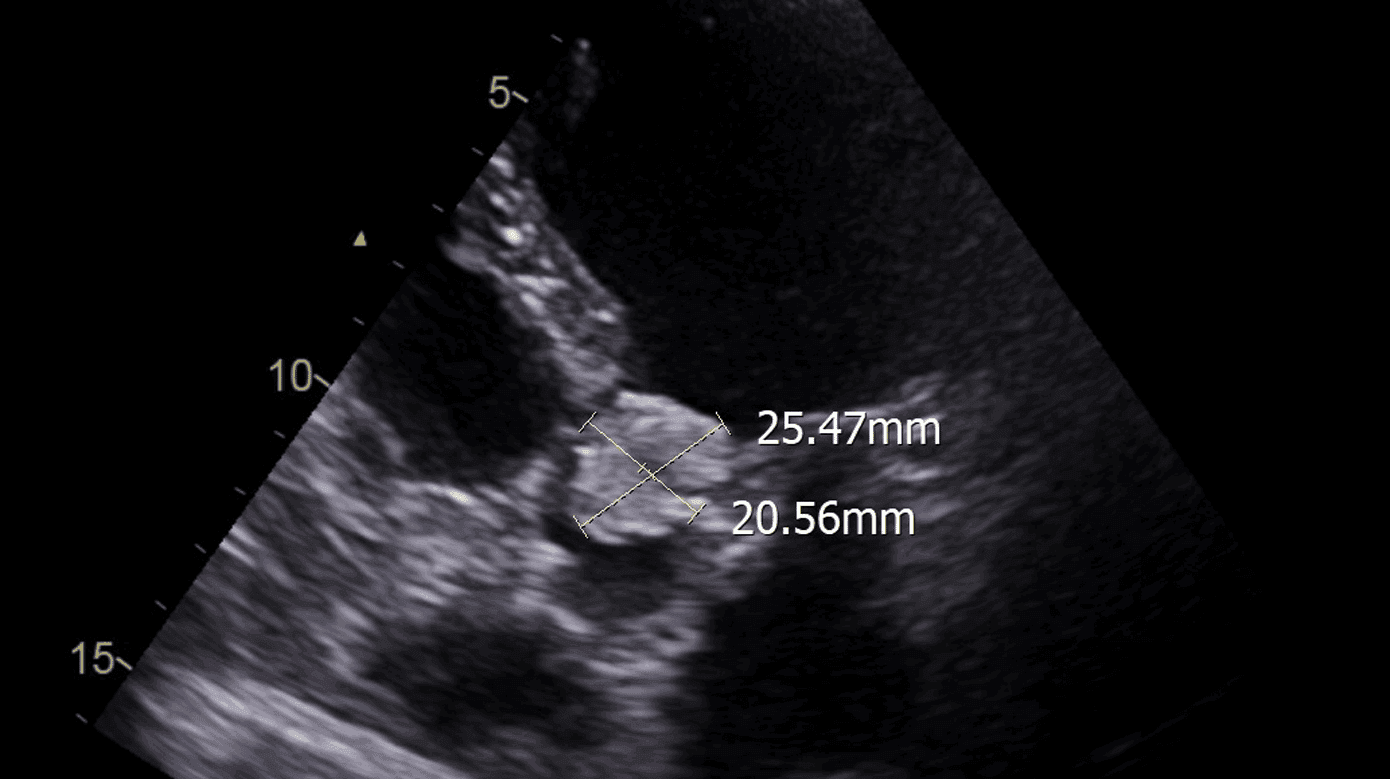

To måneder senere blev patienten genindlagt grundet cikatricedefekt. Patienten var siden ileusoperationen blevet rollatorbruger og havde kronisk diarré. Ved eksplorativ laparotomi blev der vurderet pæne forhold intraabdominalt. Der blev foretaget bloddyrkning × 2, som tilsvarende to måneder tidligere påviste C. glabrata i to ud af to kolber, og der var intet resistenssvar. Klinisk observeredes et blodtryk på 91/58 mmHg, sinustakykardi, takypnø med behov for 4 l nasalt ilttilskud og tiltagende konfusion. Patienten var ydermere sengeliggende. En CT af thorax blev beskrevet med bilateral bronkopneumoni og bilateral pleuraeffusion. Ved en transtorakal ekkokardiografi (TTE) blev der fundet en 20 × 25 mm stor, mobil vegetation på aortaklappen (Figur 1), moderat obstruktion, gradient over aortaklappen på 54 mmHg, let aortainsufficiens uden større klapdestruktion og venstre ventrikel ejection fraction på 60%. Patienten diagnosticeredes således med C. glabrata-endokarditis. Der blev afstået fra transøsofagal ekkokardiografi, da diagnosen var sikker ud fra TTE. I samråd med Rigshospitalet blev det vurderet, at kirurgisk behandling ikke var udelukket, men at der forventedes et langvarigt, kompliceret forløb med høj mortalitetsrisiko. På baggrund af den medtagne kliniske tilstand og samtidig pneumoni blev det besluttet i første omgang at tillægge antifungal behandling med i.v. echinocandin og forsøge at optimere tilstanden inden senere revurdering af, om patienten skulle flyves til Rigshospitalet til kirurgisk behandling. I løbet af de kommende to døgn blev patienten ukontaktbar og døde kort inden, den antifungale behandling ankom til Grønland.